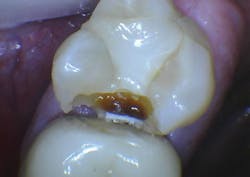

Additional clinical time for dentists: A small Class II resin-based composite can usually be placed in a short time, while larger composites require much more time and expertise (figure 3). Third-party payers pay the same regardless of the size of the restoration. If lesions are not identified early, the dentist must spend more time preparing the tooth and then placing and finishing the restoration. Not only does the patient suffer shorter restoration longevity, additional future replacement of the restoration, and higher cost, but the dentist also expends more time and effort for a large restoration and receives less proportionate revenue for the services (figures 4a and 4b).

Figure 3: Note the presence of a lesion on the distal surface of the mandibular second premolar, which appears to be about halfway through the enamel. Most current digital radiographs show only about half of the actual depth of initial caries as shown in the partly finished prep. The lesion was already into the dentin about 1 mm as shown on this partially completed tooth preparation.

Figures 4a and 4b: The restored premolar tooth is the same premolar shown in Figure 3. Such small restorations serve far longer than large ones as shown in the molar.